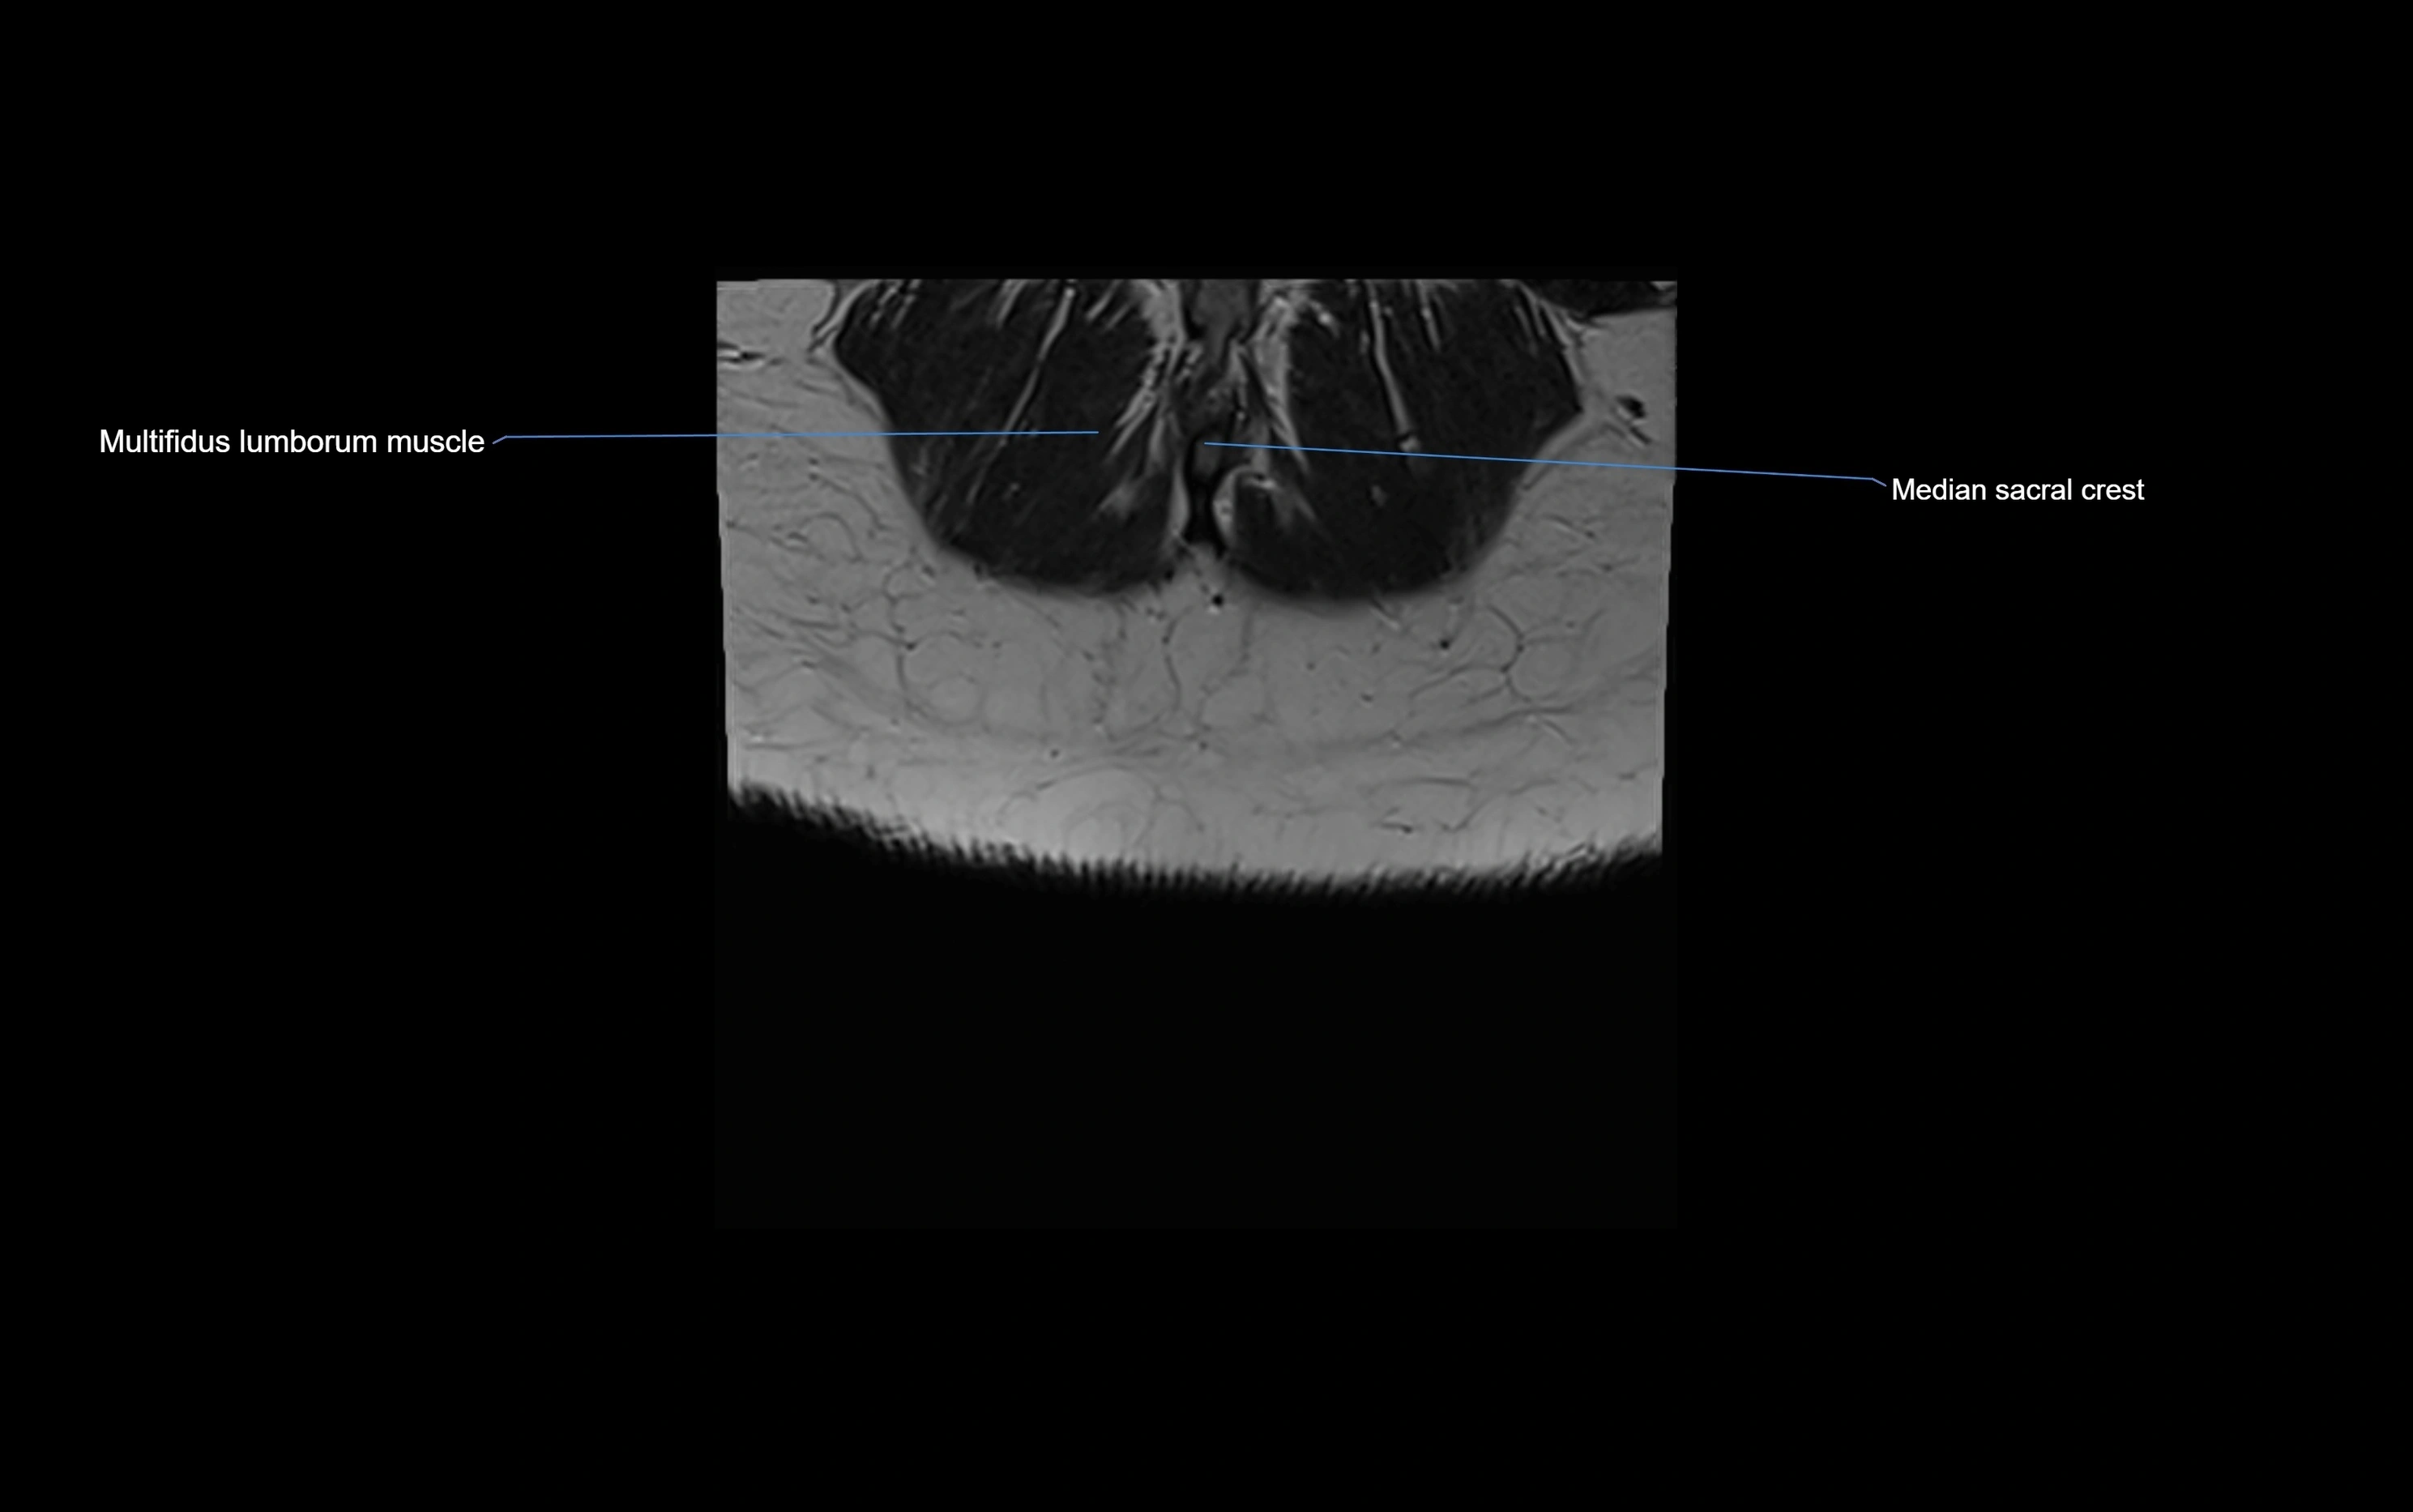

MRI image

image